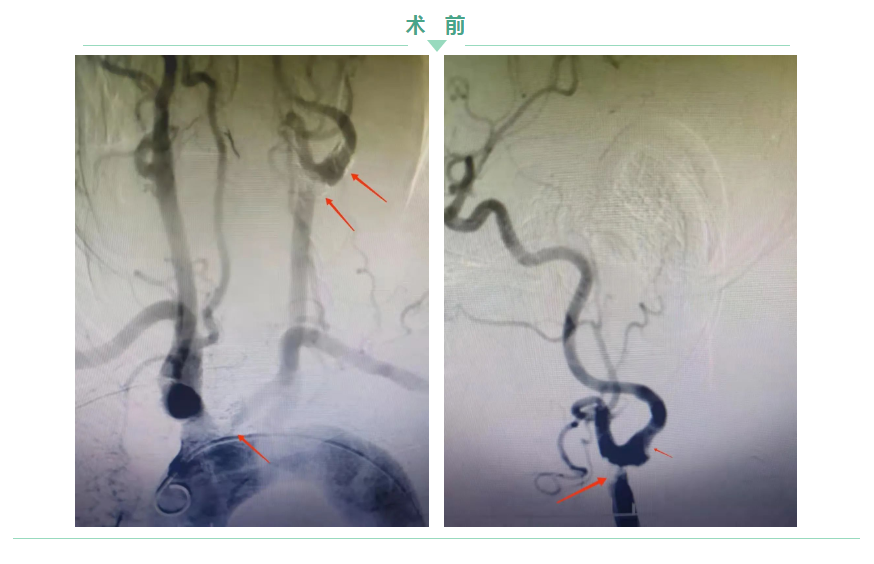

74歲王大爺頭暈、頭痛一個多月了,自己在家吃藥一直沒什么效果。北大醫(yī)療淄博醫(yī)院神經(jīng)內(nèi)科主任鐘濤接診后,經(jīng)過系統(tǒng)檢查,發(fā)現(xiàn)王大爺左頸總主動脈有兩處狹窄分別達80%、90%。一條血管多處重度狹窄,如果發(fā)生閉塞,將會產(chǎn)生災(zāi)難性的后果,決定為其實施雙支架植入術(shù)?!皶r間就是生命!”雖然手術(shù)極為復(fù)雜,但家屬的信任打消了專家們的疑慮。

神經(jīng)內(nèi)科主任鐘濤與血管介入科主任劉綿春,聯(lián)合為王大爺實施支架植入術(shù),雖然在手術(shù)過程中遇到了各種難題,但鐘主任與劉主任“見招拆招”,手術(shù)順利結(jié)束。 兩處支架完全覆蓋患者的狹窄斑塊,血流通暢了。